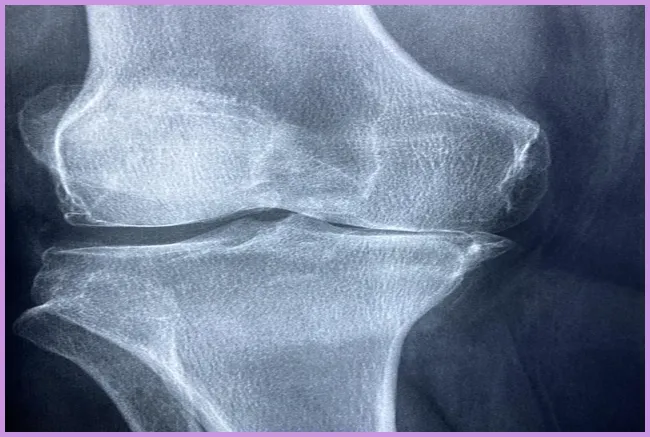

류마티스 관절염은 면역 시스템이 자신의 관절을 공격하여 염증을 발생시키는 자가면역 질환입니다. 이는 지속적인 통증과 불편함을 유발하며, 관절의 기능을 저하시킬 수 있습니다. 초기 단계에서는 일반적인 증상으로 시작하여 시간이 지남에 따라 악화될 수 있습니다. 이 질환은 주로 손, 발, 무릎과 같은 관절에 영향을 미치는 경향이 있습니다. 그렇다면 이 질환의 초기 증상은 무엇일까요?

관절염 초기 증상 탐색

관절염의 초기 증상 중에서도 가장 눈에 띄는 것은 관절의 통증입니다. 이 통증은 아침에 더욱 심해지는 경향이 있으며, 예를 들어 아침에 일어나서 발가락의 통증으로 인해 걷기가 힘들어질 수 있습니다. 이러한 증상은 해당 관절의 염증에 의해 발생합니다. 초기 증상이 나타났다면 전문가와의 상담을 통해 조기에 대처하는 것이 매우 중요합니다.